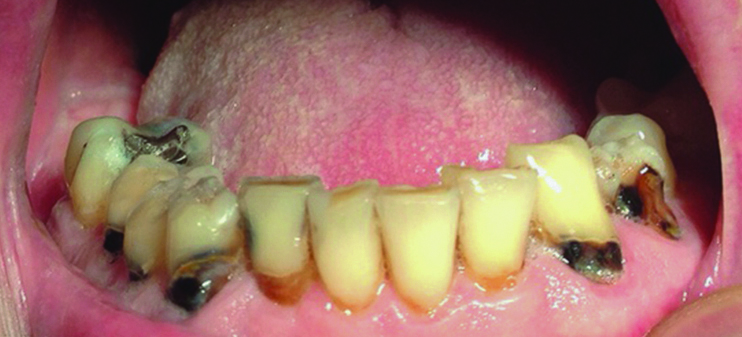

Finally, a lack of saliva may increase the incidence of oral fungal infection, especially candidiasis. Angular cheilitis and atrophy of the tongue papillae or buccal mucosa are common oral mucosal symptoms in patients with xerostomia.36 Closely linked with changes in the oral microbial flora, these conditions are caused mainly by Candida species, which are present in the oral mucosa, intestines, and skin.36,37 The interactions with salivary proteins partly affect Candida oral colonization.38 The oral microbiota may change, thereby increasing the risk for opportunistic infections (Figure 2). Table 2 summarizes the oral complications and other consequences seen in patients with xerostomia.

Fig 2. Pseudomembranous candidiasis in a patient with xerostomia.

Figure 2